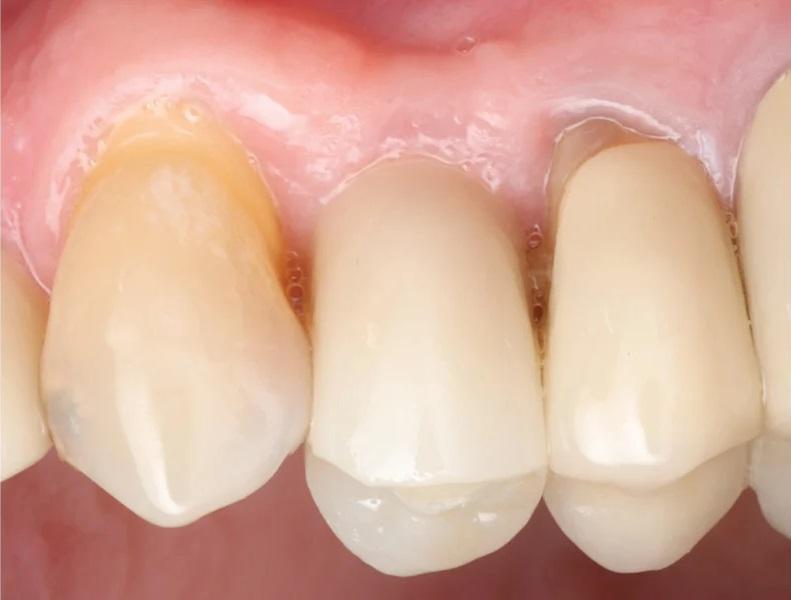

Фото 12. Вестибулярный вид здоровых мягких тканей через 5 месяцев после удаления первого премоляра верхней челюсти слева.

На контрольном осмотре через 16 месяцев клиническая оценка выявила сохраненный объем гребня и стабильную кератинизированную мягкую ткань (Фото 22 и Фото 23). Рентгенологический анализ подтвердил стабильный уровень кости вокруг имплантата № 2.4 и положительные рентгенологические изменения, свидетельствующие о регенерации тканей на медиальной поверхности зуба № 2.5, включая восстановление периодонтальной связки (Фото 24).

Фото 22 и Фото 23. На контрольном осмотре через 16 месяцев: интраоральный окклюзионный вид (Фото 22) и латеральный вестибулярный вид (Фото 23) демонстрируют реставрацию на имплантате с винтовой фиксацией.